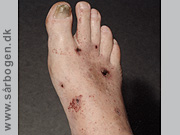

Efter tåamputation

Zoom